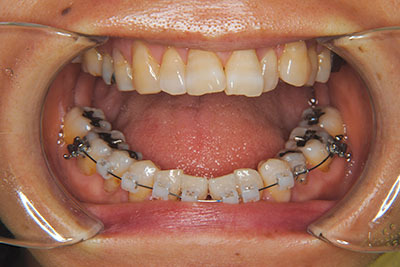

子供の頃に矯正治療を行う方が治療期間が短く済むというのは、確かですが、矯正治療は患者様の意識も重要です。

いくら歯が動き易くとも、本人がやる気でなければ効果は出ませんし、むし歯発生のリスクも高まります。おとなの方は顎の成長が終わっているため、治療の計画が立てやすいとも言えます。「もう大人だから…」とあきらめず、一度ご相談ください。